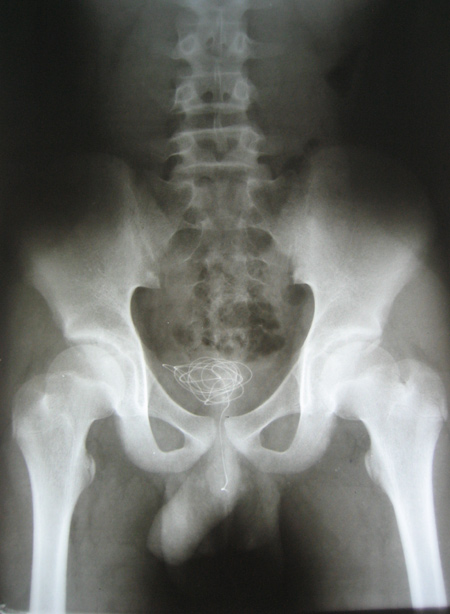

Sợi dây điện nằm gọn trong bàng quang của trẻ

Xét nghiệm hình ảnh, các bác sĩ thấy cả sợi dây nằm gọn trong bàng quang của P., với một đầu còn nằm lửng lơ trong niệu đạo. Khi “vật chứng” được lấy ra ngoài, các bác sĩ đều ngạc nhiên vì sợi dây điện dài đến 1 m, đường kính khoảng 3 mm, lõi đồng còn bọc nhựa.

Dị vật được lấy ra khỏi bàng quan của P.

Theo bác sĩ, đây là trường hợp may mắn vì hai đầu lõi đồng của sợi dây điện không lộ ra nếu không đã có thể gây rách niệu đạo, bàng quang của P. Phần may mắn tiếp theo là sợi dây dài như thế mà không tạo nút thắt nên bác sĩ có thể nội soi gắp dị vật qua đường tự nhiên, chứ không cần mổ mở ổ bụng.